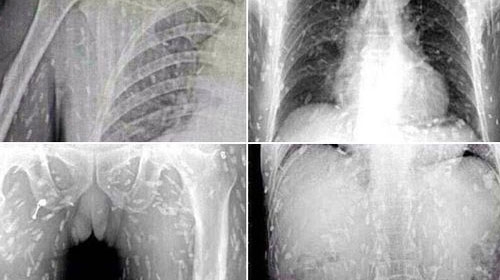

ชายจีนคอปลาดิบสุดช็อก เอกซเรย์เจอพยาธิทั่วตัว